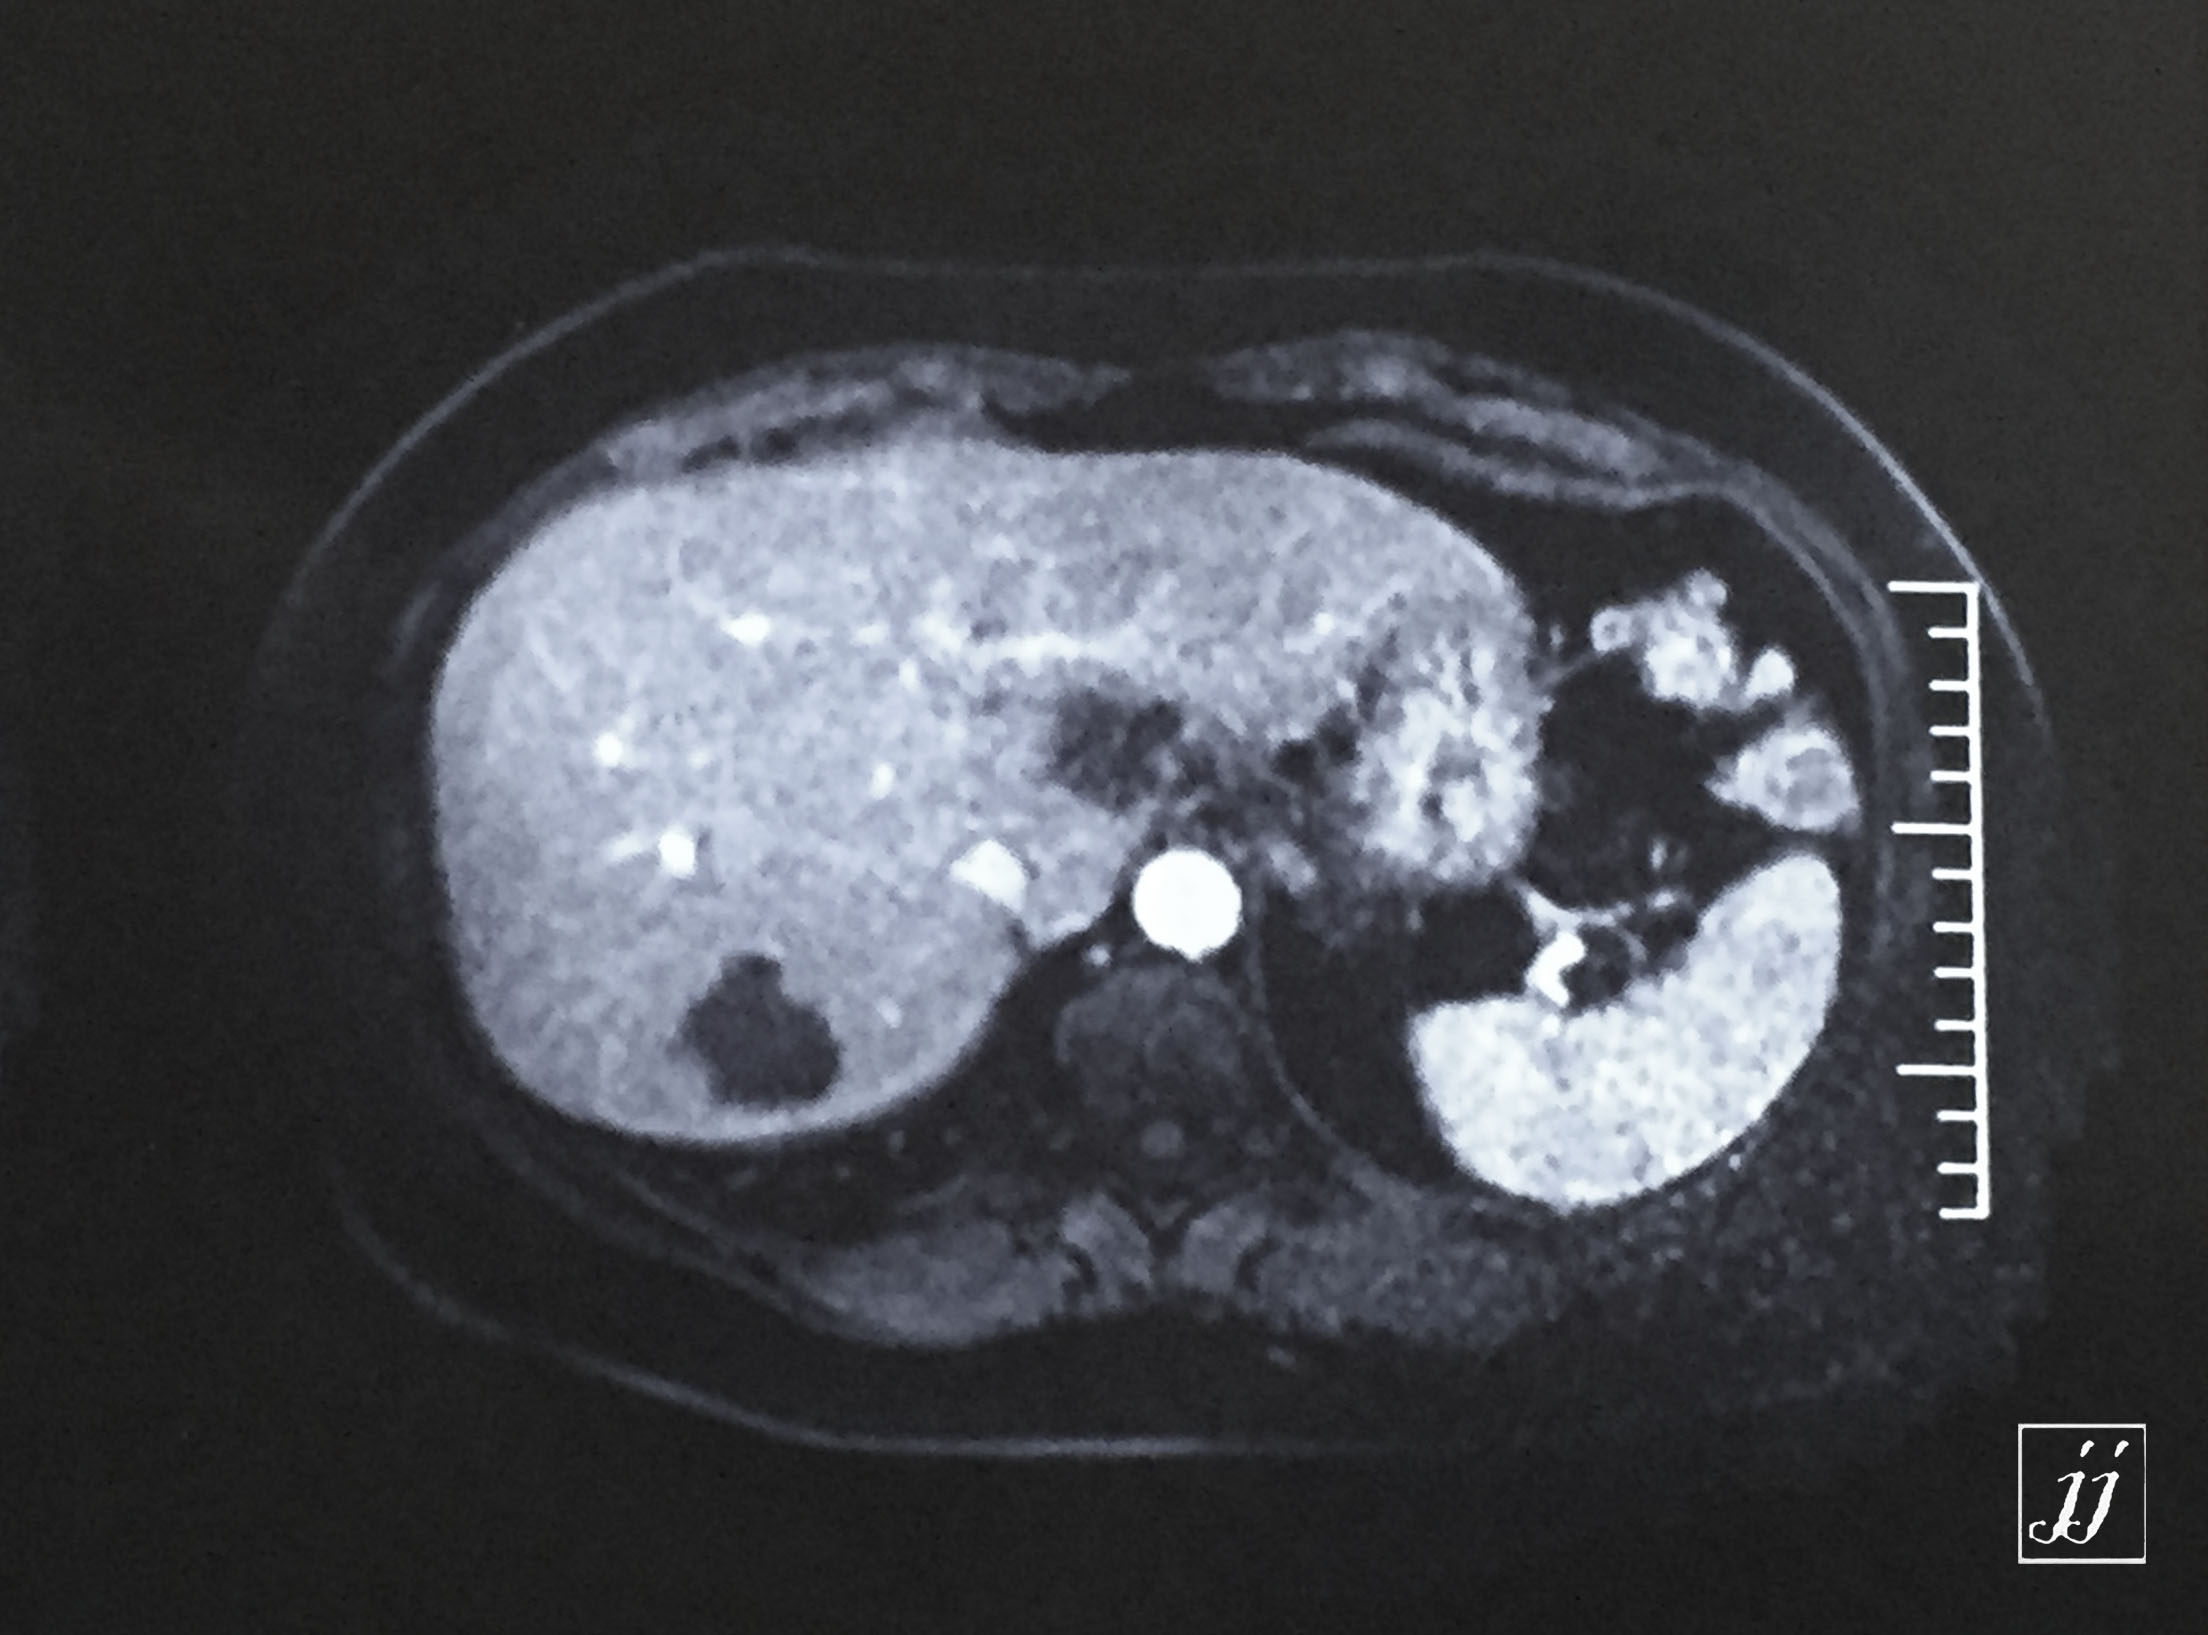

Abdomen- liver hemangioma (4)